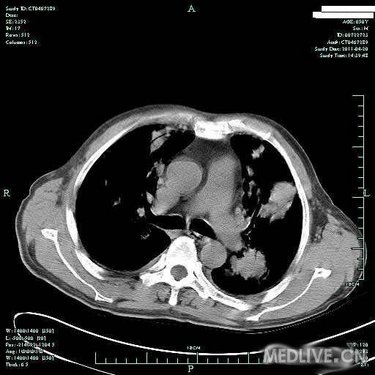

病史特点:患者于3月余前受凉后出现发热,体温为39.0摄氏度左右,伴咳嗽,为阵发性咳嗽,有咳痰,色白,有咽痛,无鼻塞及流涕,至当地诊所输液(具体不详)治疗后,效果不明显。于80天前入住当地医院,住院期间查胸部CT提示:双肺弥漫性结节影,纤支镜:双叶段粘膜轻度充血、水肿,痰找脱落细胞阴性,行左下肺经皮肺穿刺针吸细胞学未见异形细胞,曾予哌拉西林/他唑巴坦针、利福平、氟康唑针等治疗后,仍有反复发热,体温高达39.0摄氏度左右,发热时有气促感,无胸痛、头痛及心悸感。于2月余前至我院住院,CRP41.80mg/L,肺CT增强:两肺多发病灶,肿瘤不能排除,建议穿刺活检;气管镜检查:两侧支气管均通畅,未见新生物,气管镜刷片、肺泡灌洗液均未见肿瘤细胞;进一步行肺穿,肺穿刺涂片找到坏死组织,涂片未见肿瘤细胞,穿刺病理:(右)肺组织慢性炎伴坏死及淋巴组织增生;骨髓活检:造血细胞增生活跃伴散在T细胞浸润。予以出院带药HRE诊断性抗结核+SMZco治疗,患者用药不规则,仍有反复发热,最高达40摄氏度,伴畏寒,予退热药处理后热退,伴少量咳嗽及呕吐,无明显咳痰,复查肺部CT病灶对比前片增多、增大,为进一步诊治收住入院。

T 37.2℃,R 20次/分,P 82次/分,BP 114/79mmHg,神清,精神偏软,浅表淋巴结未及肿大,双肺呼吸音粗,未及明显干湿啰音,心律齐,瓣膜区未闻及病理性杂音,腹平软,无压痛及反跳痛,肝脾肋下未及,双下肢无浮肿,右上肢肌力IV级,握力差。

血常规(五分类)(病房):白细胞计数3.8×10E9/L,中性粒细胞(%) 84.8%,淋巴细胞(%) 4.7%,血红蛋白106g/L,血小板计数279×10E9/L。

血生化:总蛋白50.3g/L,白蛋白27.4g/L,球蛋白22.9g/L,白球蛋白比例1.2。 ANCA,MPO,PR3等检查未见明显异常。 癌胚抗原7.8ng/mL,神经元特异性烯醇化酶44.0。